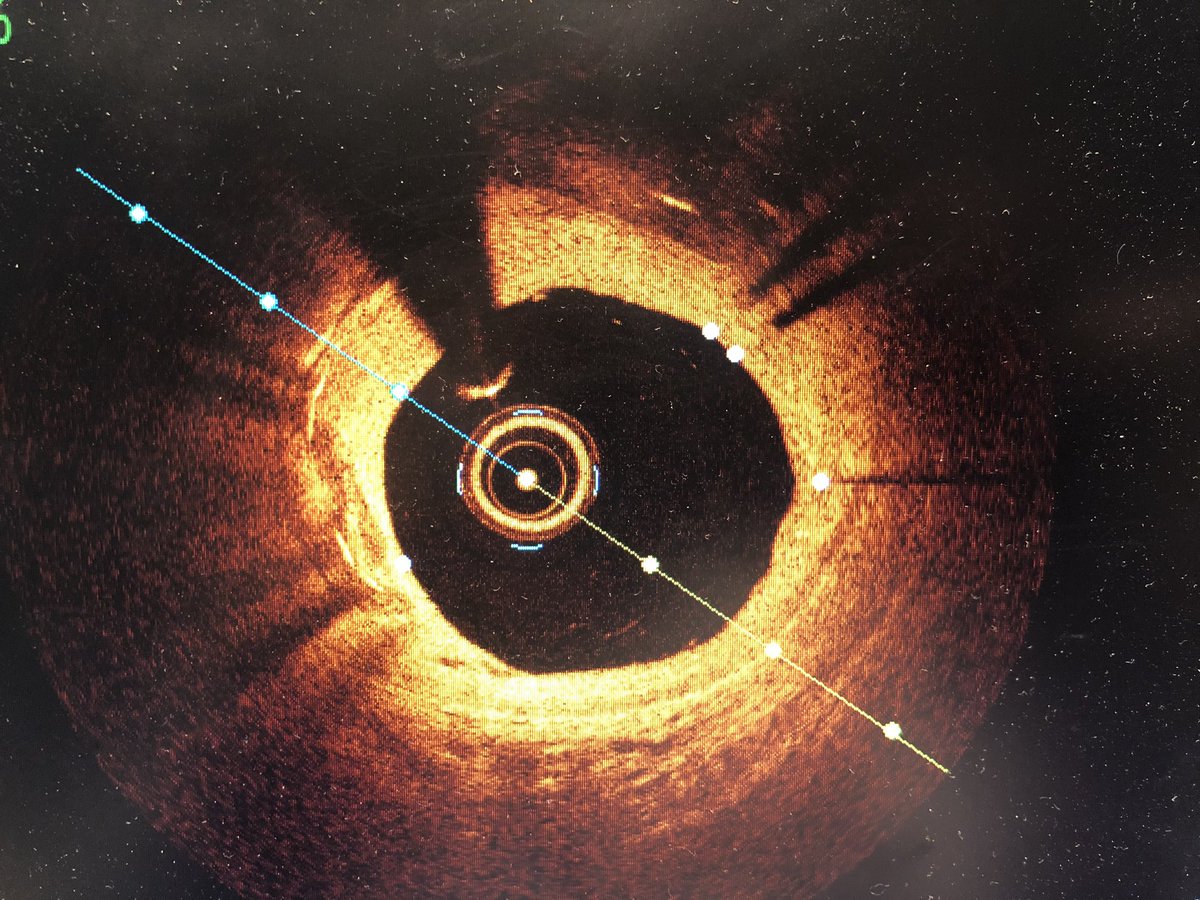

Doscondos@Doscondos·9 KasCalcium at 12-2 behind two layers. Balloon slightly under expanded. Used laser with contrast. How do you modify this lesion? @DanyJacob87 @ShariqShamimMD @SukhNijjer @SVRaoMD @DrMauricioCohen @Drroxmehran @CAThompson99 @DKarmpaliotis @rwyehÇevir English12601

Doscondos@Doscondos·9 KasWhat is the mechanism for ISR in this two year old stent? Neo-atherosclerosis or intimal hyperplasia? @GreggWStone @ziadalinyc @TheNarulaSeries @J_M_McCabe @grantham_aaron @mucox25 @Dr_Lux_DO @DrSheilaSahni @willsuh76 @Dr_Bitar @HashimKhan_1Çevir English45200